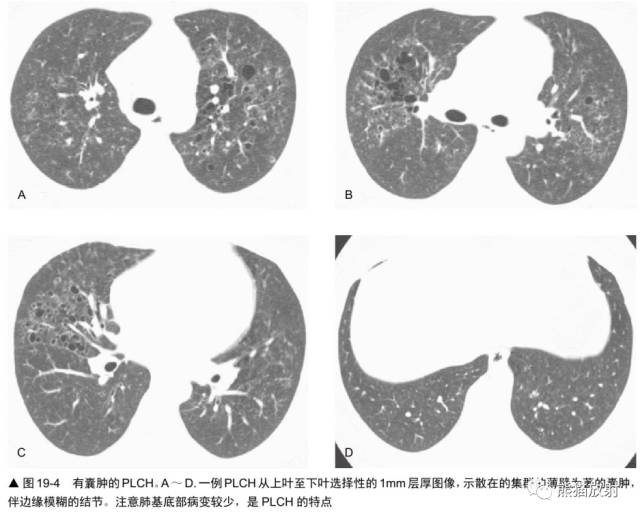

LAM中的肺囊肿与肺朗格汉斯细胞组织细胞增生症(PLCH)中描述的非常相似然而,3种表现常可以区别这两种疾病。

最后,要强调的是PLCH是典型的与吸烟相关的疾病之一,而LAM已经证明无此种与吸烟的关系。

PLCH是一种少见病,常发生在20-40岁的年轻人中,虽然可发生在任何年龄。PLCH以往被称为肺嗜酸性肉芽肿、肺组织细胞增生症X,其典型表现为孤立的,累及单器官的病变,虽然也可是多器官、多系统疾病的一种表现。

病变主要分布在上、中肺部,基底部相对不累及。